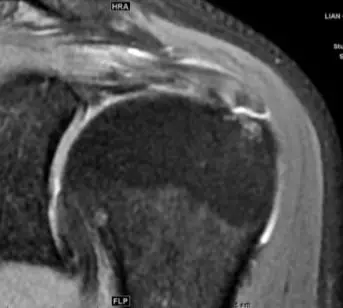

冈上肌腱全层撕裂,累及冈下肌腱。

看肌腱撕裂时要至少在两个平面看:

斜冠、斜矢上的图像

MRI可帮助确定肌腱损伤的损伤部位和严重程度,尤其是MRI可以清晰的显示肩袖的部分撕裂,对诊断具有较高的价值。在MRI对肩袖损伤的诊断上,至少在2个平面评估,注意肌腱变性与撕裂信号鉴别,肌腱的形态,如果有肌腱损伤,则要看是否累及肌肉,评价肌肉的萎缩程度。